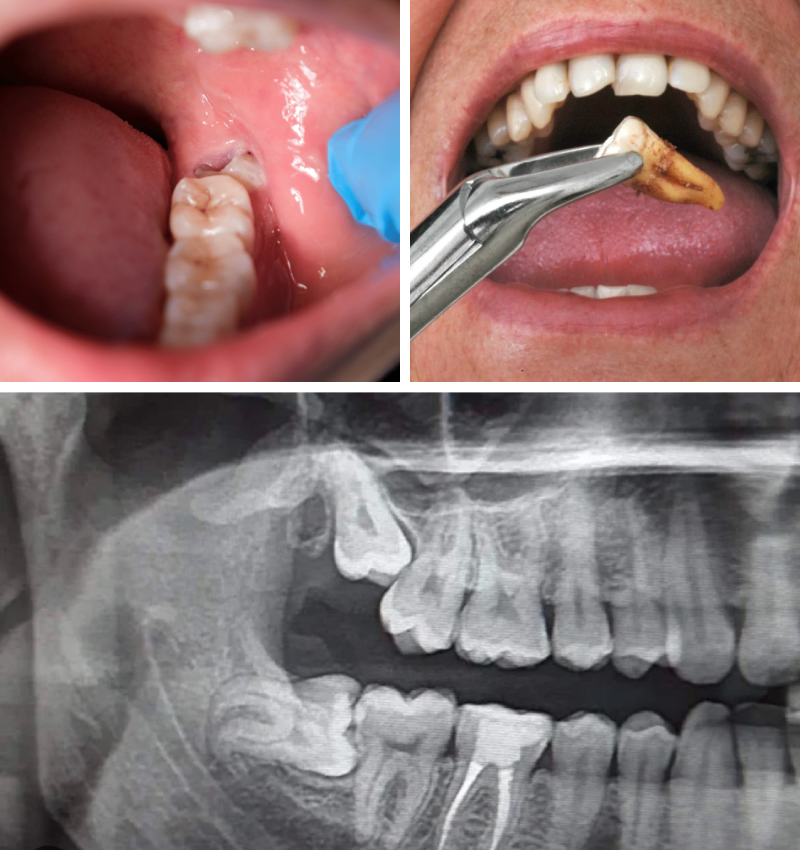

Wisdom teeth, also known as third molars, typically emerge between the ages of 17 and 25. While some grow in without issues, many people experience pain, swelling, or misalignment due to lack of space in the jaw. If left untreated, impacted wisdom teeth can lead to infection, decay, and damage to neighboring teeth.

Impaction: The tooth is trapped under the gum or growing at an angle, causing discomfort and pressure.

Impacted Wisdom Tooth Extraction

• A detailed oral exam and digital X-rays to assess the position of your wisdom teeth

• For impacted teeth, a small incision is made to safely remove the tooth